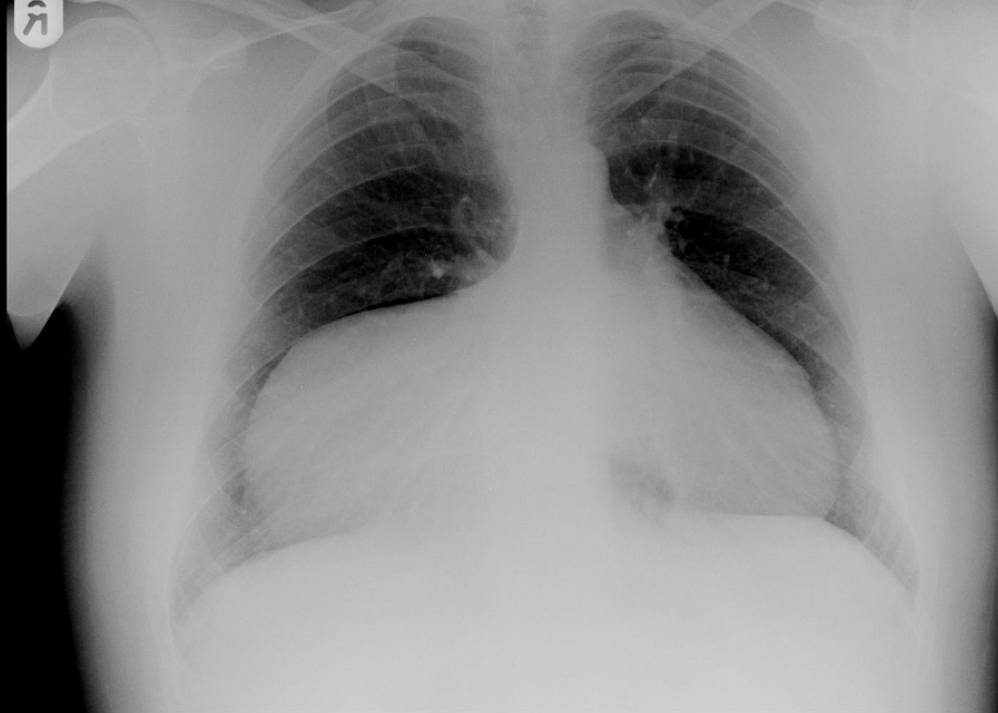

A 25 year old male, who was being investigated for a possible soft tissue tumour of the left buttock, developed symptoms of right sided pleuritic chest pain. There was no associated shortness of breath, cough or recent chest infection. There was no history of recent or previous significant blunt trauma to the abdomen or chest.

What could be the diagnosis ?